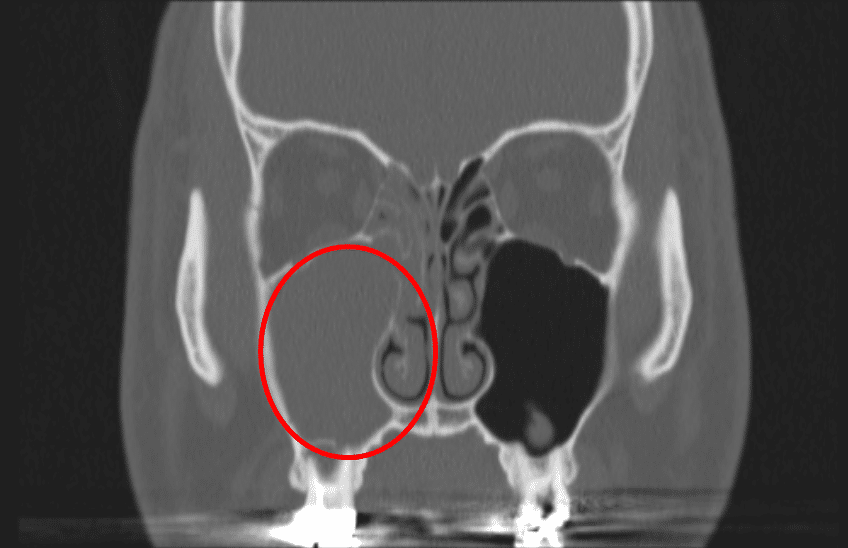

부비동은 한글 용어로 ‘코곁굴’이라고도 합니다. 풀어서 말씀드리자면 ‘코 곁에 있는 굴’이라는 말인데, 이러한 굴은, 사람에 따라 다를 수 있지만, 보통 머리에 4쌍, 8개가 있습니다. 이 8개의 부비동들은 모두 코 안(비강)에서 연결되어 있는데, 그 입구는 구불구불한 통로 형태이며 굴 자체의 크기에 비해 매우 작습니다. (영화에 나오는 동굴들이 안은 넓은데 입구는 작은 것처럼 말이죠) 그렇지만 부비동을 덮고 있는 점막 표면의 섬모 운동이 비강과 부비동 사이의 물질들의 이동을 도와주기 때문에, 부비동이라는 굴 안에 이물질들이 쌓이지는 않습니다.

그렇다면 부비동염은 무엇이고, 만성 부비동염은 무엇일까요. 부비동염은 말 그대로 이 부비동에 염증이 생긴 것, 즉 부비동 점막의 염증성 질환을 통칭하는 질환입니다. 그리고 바이러스나 세균이 부비동 안으로 침입한 후 점막의 염증이 생긴 직후 상태를 ‘급성 부비동염’이라고 하고, 이러한 급성 부비동염이 회복되지 않고 12주 이상 지속되는 경우를 바로 ‘만성 부비동염’이라고 합니다. 이렇게 오래 부비동염이 회복되지 않으면 원래는 깔끔하게 비어있어야 하는 굴속에 고름(농)이 쌓이게 되지요. 그래서 만성 부비동염을 ‘축농증’이라고 하는 것입니다.